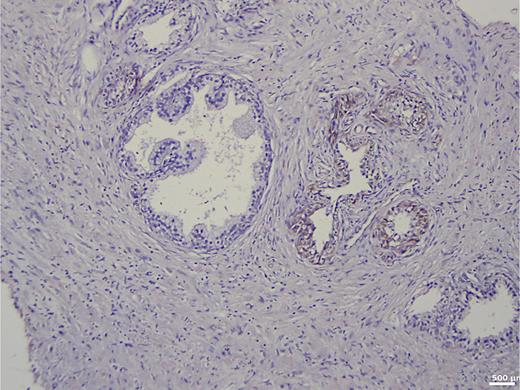

In the group of patients without carcinoma, the vast majority exhibited BSP expression of less than 1%. Twenty-nine out of thirty patients had a value below 5% (Table 1). One patient showed a BSP expression of 9%; however, the expression was observed only in basal cells in a condition of basal cell hyperplasia combined with chronic inflammation (Fig. 1). BSP expression in prostate tissue without carcinoma and without basal cell hyperplasia is shown in Figure 2.

Fig. 1.

Immunohistochemistry in prostate tissue without carcinoma and with basal cell hyperplasia.